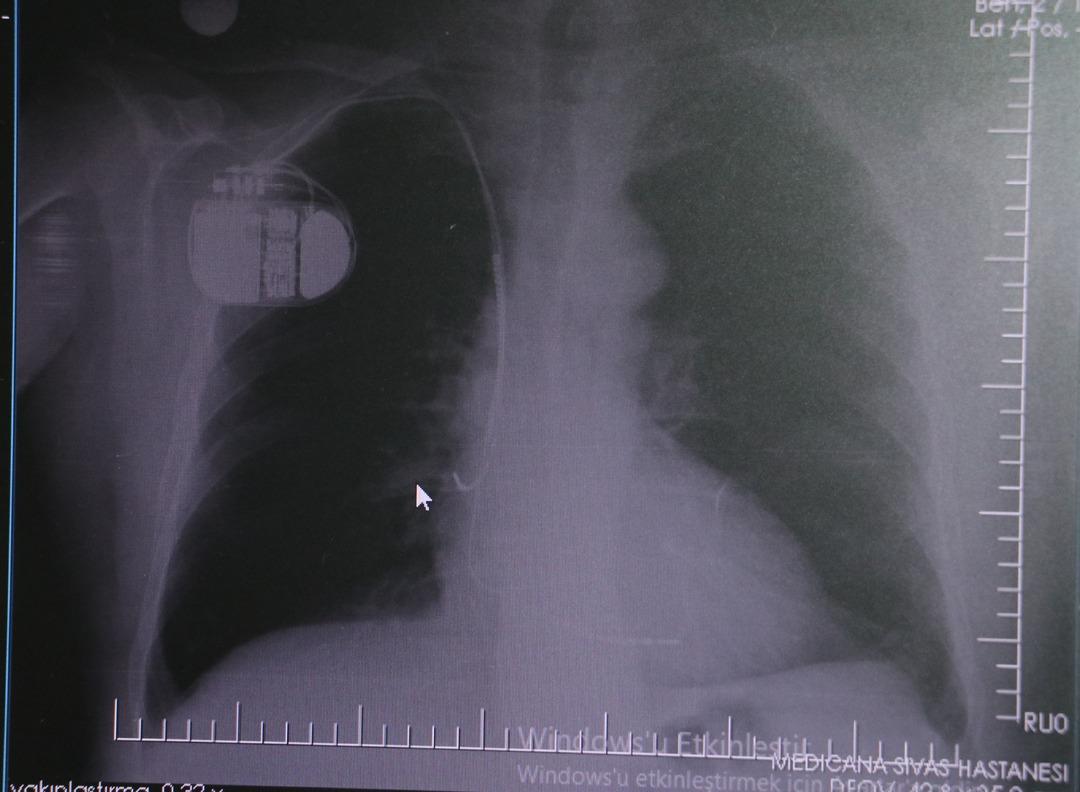

Kalp krizi sonrası kalp dokusunun zarar gördüğünü belirten İsmail Erdoğu, şöyle konuştu: “Kalp hastalığı günümüzde dünyada en sık görülen ölüm nedenlerinden biridir. Kalp hastalıklarının pek çok grubu vardır. Kalp hastalığı dediğimizde sadece kalpte stent bulunan ve damar sorunları olan kişileri kastetmiyoruz. Aynı zamanda hipertansiyon ve şeker hastalığı olan hastalar da kalp hastalığına adaydır. Toplumun yaklaşık %30-35'ini kapsıyoruz. Oldukça yaygın bir hastalıktır ve bu konuda teknolojik ve tıbbi anlamda ciddi gelişmeler yaşanmıştır. Son 30 yılda insanlar kalp rahatsızlığı nedeniyle hastaneye kaldırıldı.” “Hastaneye yattıktan sonra hayatta kalmak artık mümkün. Kalp krizinden kurtulmanın belli bir maliyeti var. Kalp krizinden sonra kalp yetmezliği ortaya çıkıyor. Kalp yetmezliği olan hastalarda aritmiler, ani ölümler gibi sorunlar ortaya çıkabiliyor. Hastaların bu uzun vadeli rahatsızlıklardan kendilerini korumak için mutlaka kalp piline ihtiyaçları var” dedi.

MR makinesine kalp pili takılmasının mümkün olduğunu belirten Erdoğu, şöyle konuştu: “Çok büyük bir ameliyat değil ama yine de ciddi bir cerrahi işlem. Kalp pili tıpta son 30 yılın en büyük gelişmesi. Aslında bilgisayarın minyatürleştirilmiş hali olup insan vücuduna yerleştirilen bir tedavi. İnsan ömrünü önemli ölçüde uzatan bir tedavi. İnsanlar şokla hayata tutunurken, pil olmasaydı öleceğini düşündüğümüz çok sayıda hastamız var. Bu özelliğimiz Kalp pili uygun hastalarda ani ölümü önler, ritmi düzeltecek sağlık uzmanı ya da defibrilatör yoksa hastayı hayatta tutmak mümkün değildir. Hastalarımız “kalp pilim var” dediğinde hastalıktan kurtulurlar. Örneğin mikser kullanmak ya da kolu sallayacak herhangi bir hareket kalp pilini olumsuz etkileyebilir. Soğuk havalarda vücutta meydana gelen şiddetli titremeler kalp pilinin hafızasını karıştırıp gereksiz şoklara neden olabilir.